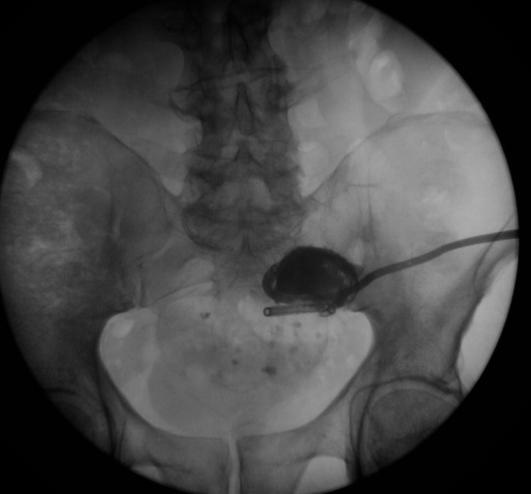

病例2 乙状结肠憩室瘘

第18天